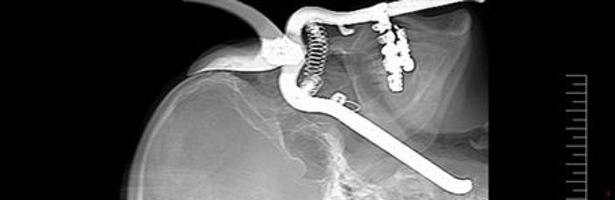

Visto que el tema médico tiene su público en la franja del late night, Discovery Max ha decidido probar la eficacia de este nuevo formato, 'Urgencias punzantes'. Desde verjas a piezas de aviones, de anillos de compromiso a una cubertería completos o cemento. El nuevo programa da la bienvenida a una realidad verdaderamente asombrosa: la de los artículos incrustados en el cuerpo humano.

La serie, integrada por seis entregas de una hora de duración cada una, narra los sucesos más extraños que acabaron con los protagonistas de la serie 'aseteados' por accidente y con una situación médica de riesgo extremo de complicada, aunque no imposible, solución. Situaciones bizarras y asombrosas que pueden enseñar no sólo a extremar las precauciones, sino a mantener el control cuando lo más incontrolable se apodera de las personas.

El primer episodio muestra el caso de una niña escocesa que nunca imaginó que un inocente paseo por la calle acabase con una valla metálica clavada en su propia cara. Otro de los casos más llamativos es el de un jardinero que, tras un descuido con la máquina cortacésped, terminó con las tijeras de podar en su cráneo.